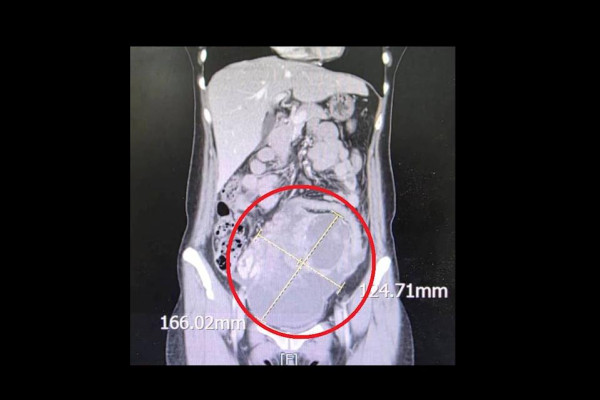

然而,經醫生詳細檢查後,赫然發現她腹部藏有一個直徑達 16 公分的巨大腫瘤。抽血檢驗更發現,她的癌症指數(CA-125)竟然狂飆至 900 U/ml,對比正常值應為小於 35 U/ml,足足超標了幾十倍之多。大千綜合醫院婦產科劉榮啟醫師見狀,立即為她緊急安排手術,切除子宮及兩側卵巢,以防癌細胞進一步擴散。